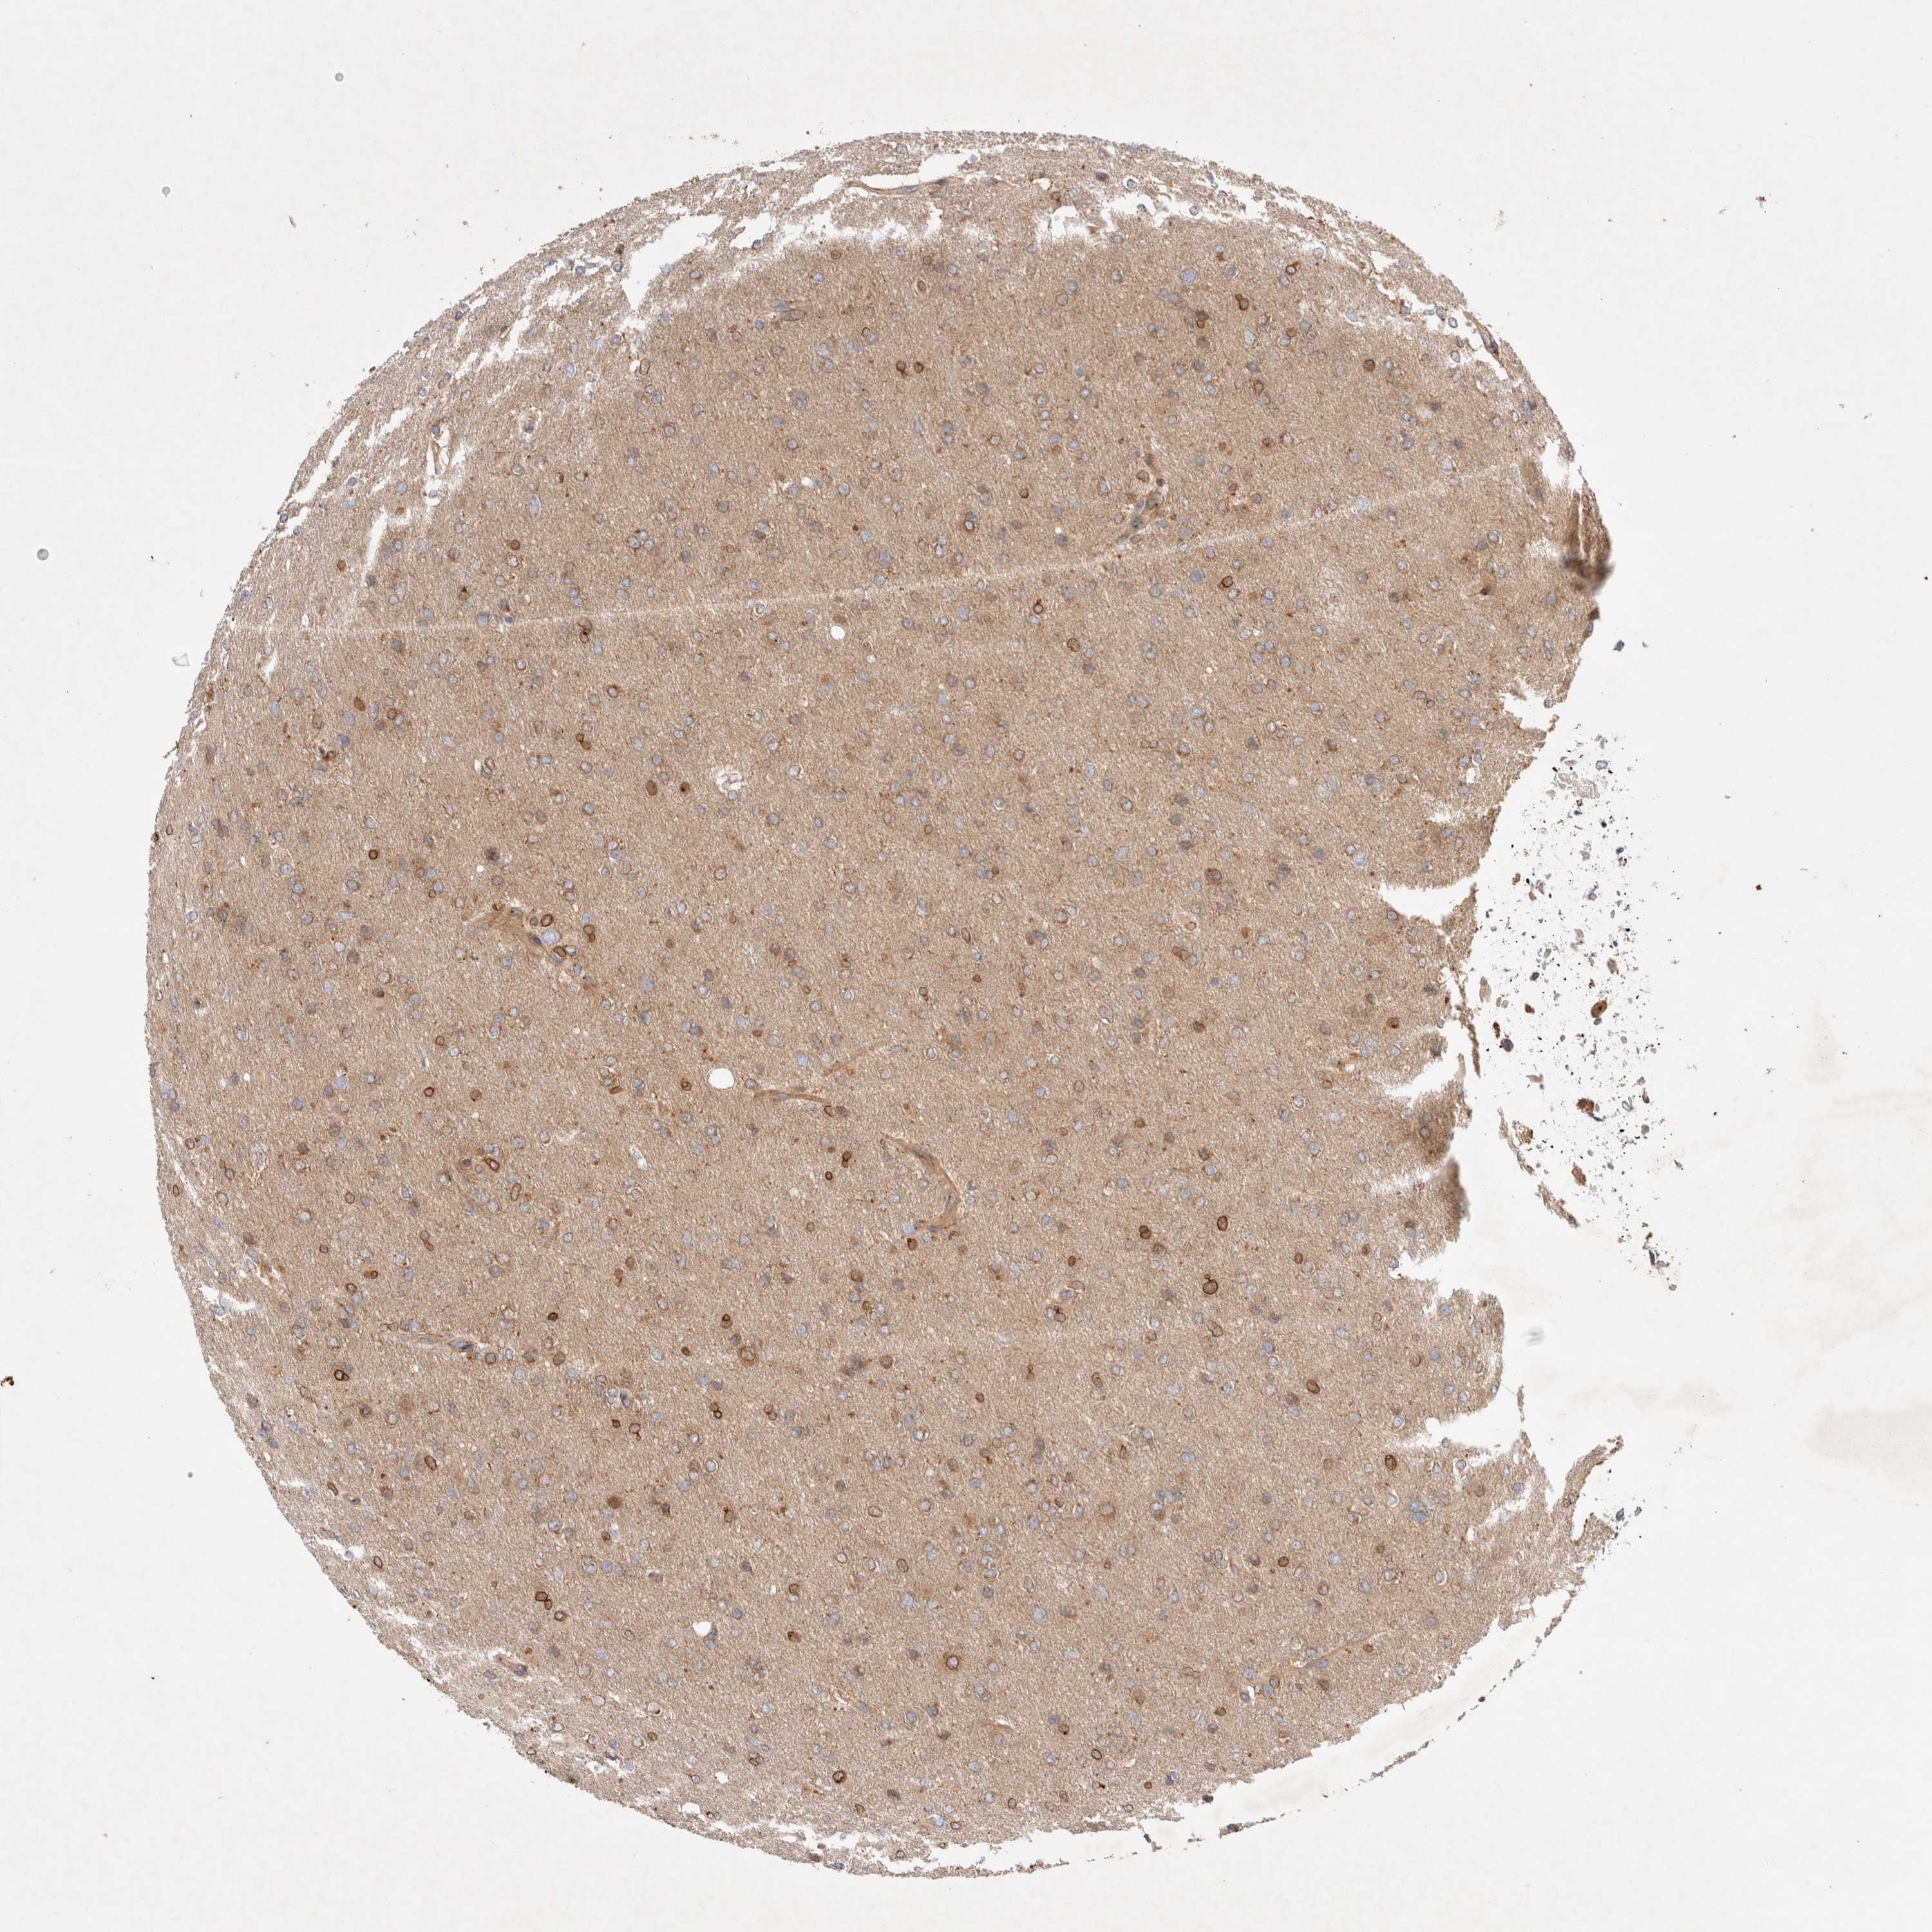

GLIOMA - Protein expressioni

A mouse-over function shows sample information and annotation data. Click on an image to view it in a full screen mode. Samples can be filtered based on level of antibody staining by selecting one or several of the following categories: high, medium, low and not detected. The assay and annotation is described here.

Note that samples used for immunohistochemistry by the Human Protein Atlas do not correspond to samples in the TCGA dataset.

Antibody stainingi

Antibody staining in the annotated cell types in the current human tissue is reported as not detected, low, medium, or high, based on conventional immunohistochemistry profiling in selected tissues. This score is based on the combination of the staining intensity and fraction of stained cells.

Each image is clickable and will lead to virtual microscopy that enables deeper exploration of all samples and also displays staining intensity scores, fraction scores and subcellular localization as well as patient and tissue information for each sample.

Antibody HPA026635

Staining

High

Medium

Low

Not detected

Intensity

Strong

Moderate

Weak

Negative

Quantity

>75%

75%-25%

<25%

None

Location

Nuclear

Cytoplasmic/membranous

Cytoplasmic/membranous,nuclear

Glioma, malignant, High grade

Glioma, malignant, Low grade